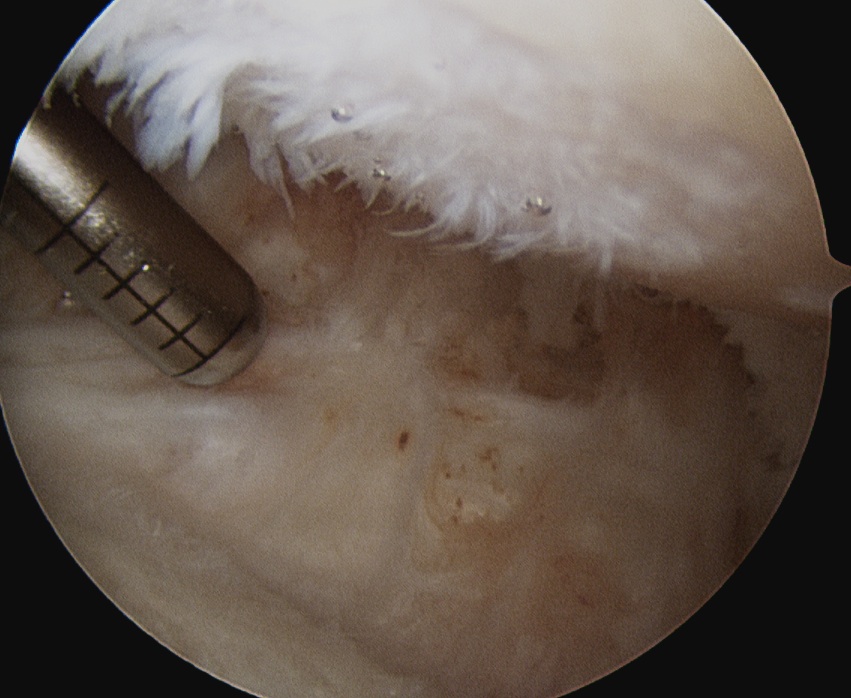

Arthroscopic Synovectomy

Kanbe et al. Eur J Orthop Surg Traumatol 2015

- arthroscopic synovectomy and capsular release for 54 RA shoulders

- mean follow up 5 years

- 67% receiving biologic treatments

- improvements in function and ROM